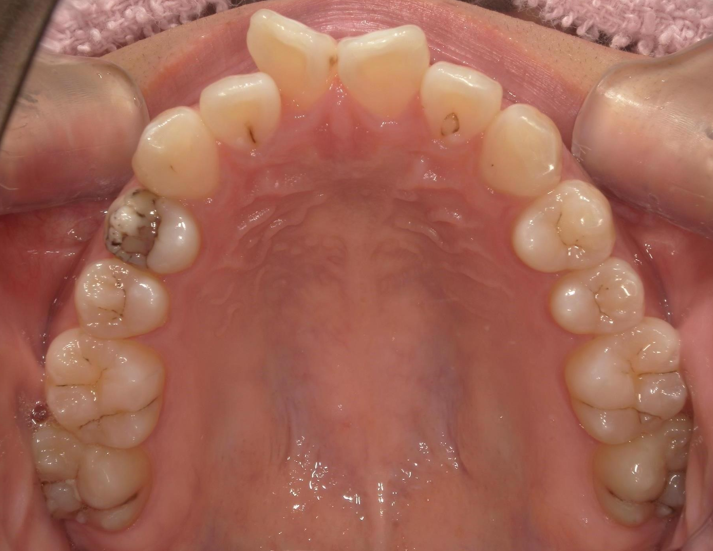

年齢 20代女性

主訴

上顎前突

前歯叢生

BEFORE